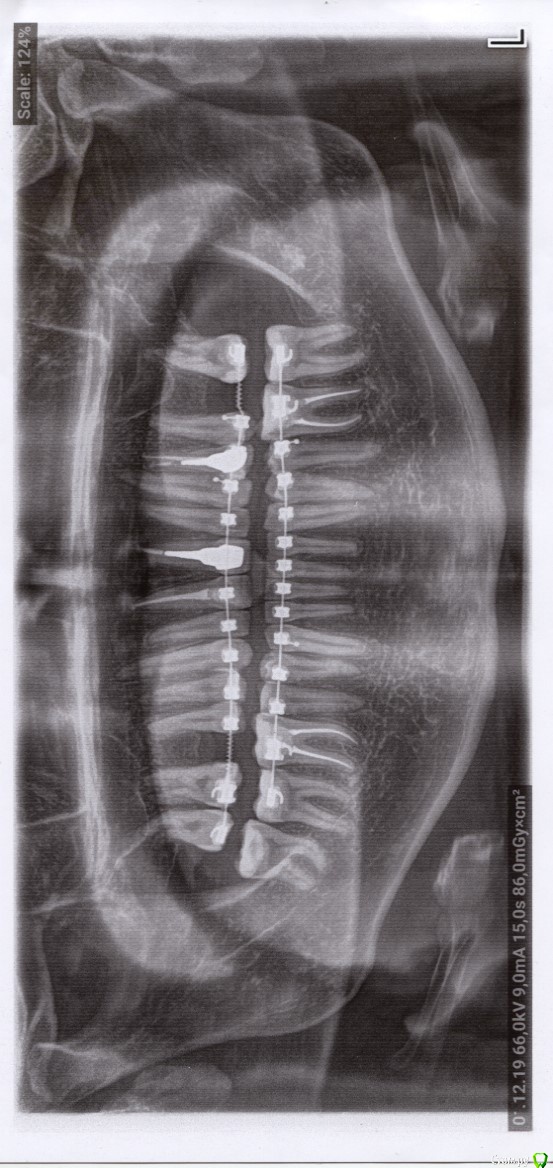

Bors Опубликовано 1 декабря, 2019 Поделиться Опубликовано 1 декабря, 2019 (изменено) Добрый день!Почти год ношу брекеты, освободилось место под имплантаты, дали добро на имплантацию. Хочу заранее перед консультациями у имплантолога узнать, что меня ожидает, что должно насторожить и т.п.На приеме у ортодонта имплантолог бегло посмотрела на освободившиеся места. Как я понял, полноценного по размерам "зуба" на месте 26-го не планируется при текущем смыкании, он будет меньше, а на месте 16-го всё будет нормально по размерам. Это нормальная практика?Хватает ли костной ткани в области данных зубов? Будет ли влиять выбор производителя/модели имплантата на необходимость наращивания костной ткани? Заранее благодарен за ответы. Ссылка на КТ (вместе с программой для просмотра):https://cloud.mail.ru/public/woLr/qTpX69i4r Изменено 1 декабря, 2019 пользователем Bors Ссылка на комментарий

Bors Опубликовано 1 декабря, 2019 Автор Поделиться Опубликовано 1 декабря, 2019 по высоте хватает, ширину нужно смотреть на Кт (качать весь архив не буду) покажите срезы областей интересаСрезы сам не делал, так как не знаю насколько правильными они будут. Прикрепляю то, что получилось. как правило не влияетЯсно. Просто частенько проскакивает в описаниях тех или иных моделей информация о том, что это идеальный вариант при недостатке костной ткани и т.п. Не совсем понятно стоит ли переплачивать за тот же Nobel или выбрать что-то дешевле. Хочется поставить и забыть на всю жизнь про этот зуб. Ссылка на комментарий